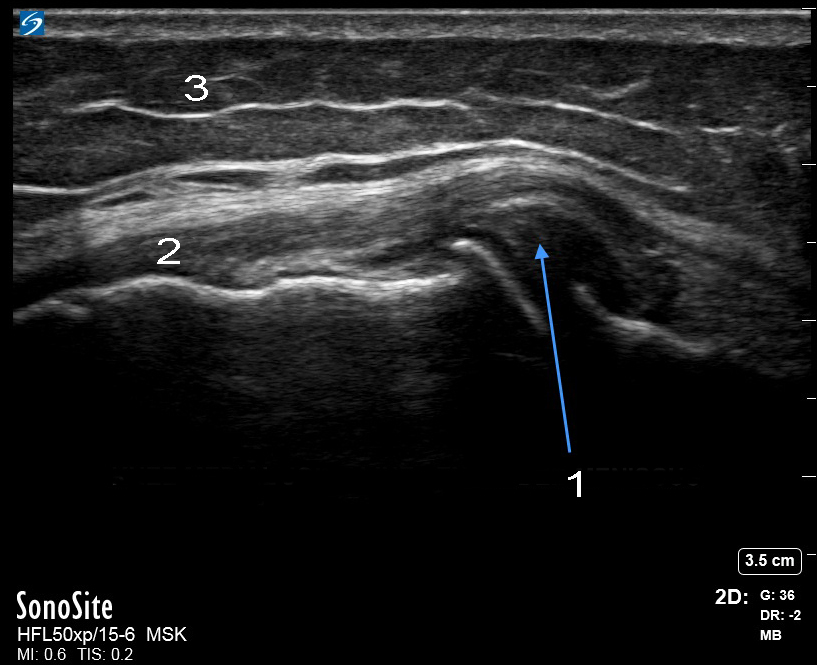

膝关节内侧半月板突出图像

内侧关节线 - 半月板突出

内侧副韧带 (MCL)

脂肪